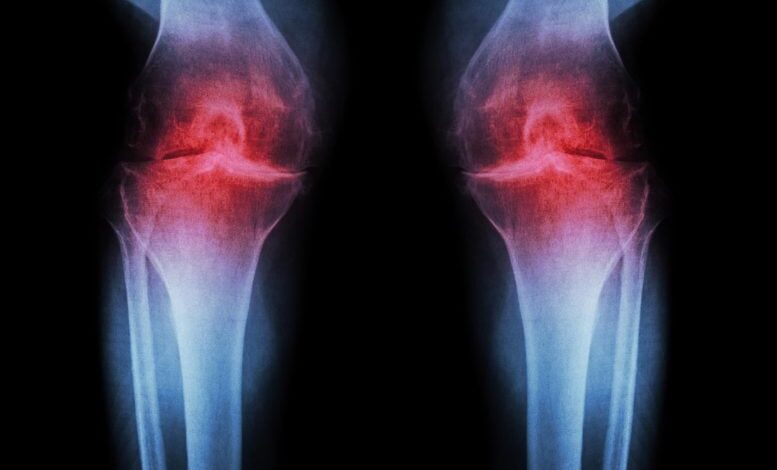

Injekce proti stárnutí obnovuje růst kolenní chrupavky a zabraňuje artritidě

Léčba, která blokuje protein související s věkem, obnovuje chrupavku ve stárnoucích a poraněných kloubech přeprogramováním stávajících buněk namísto použití kmenových buněk. Výzkumníci ze Stanford Medicine uvádějí, že blokování proteinu spojeného se stárnutím může obnovit chrupavku, která se přirozeně opotřebovává v kolenou starších myší. Ve studii nebyla injekční léčba (…)